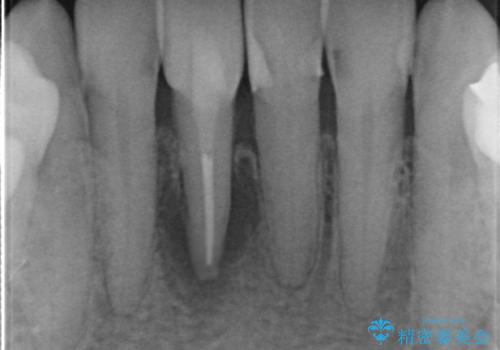

口腔内を精査したところ、右上のブリッジの内側(口蓋側)がかけており、下の前歯(右下1)には唇舌側に瘻孔を伴う大きな根尖病変ができていました。

右上のブリッジ(右上④3②)のやりかえと、下の前歯(右下1)の根管治療を行った後セラミッククラウンによる補綴治療を行いました。

精密な根管治療により、下の前歯の歯ぐきにできていた瘻孔もなくなりました。